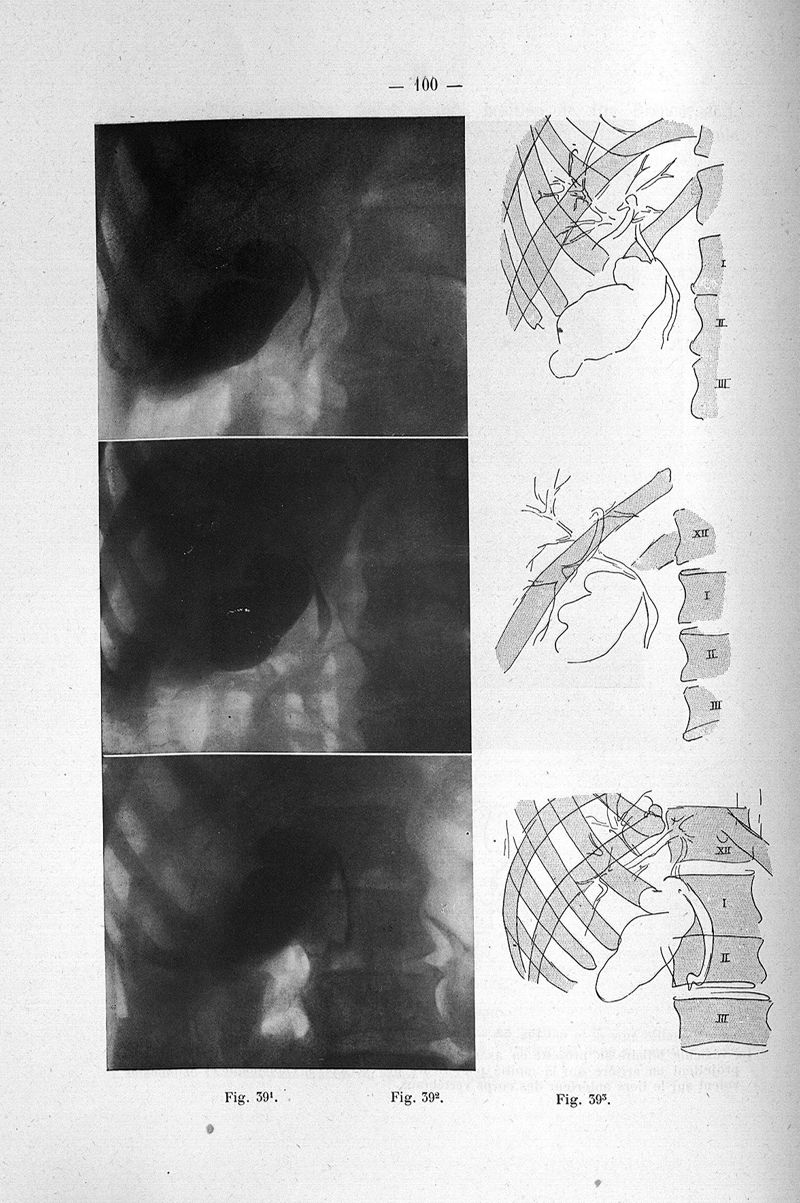

Gatellier, Jean.

Titres et travaux scientifiques

Paris, Librairie Labrousse, 1926.